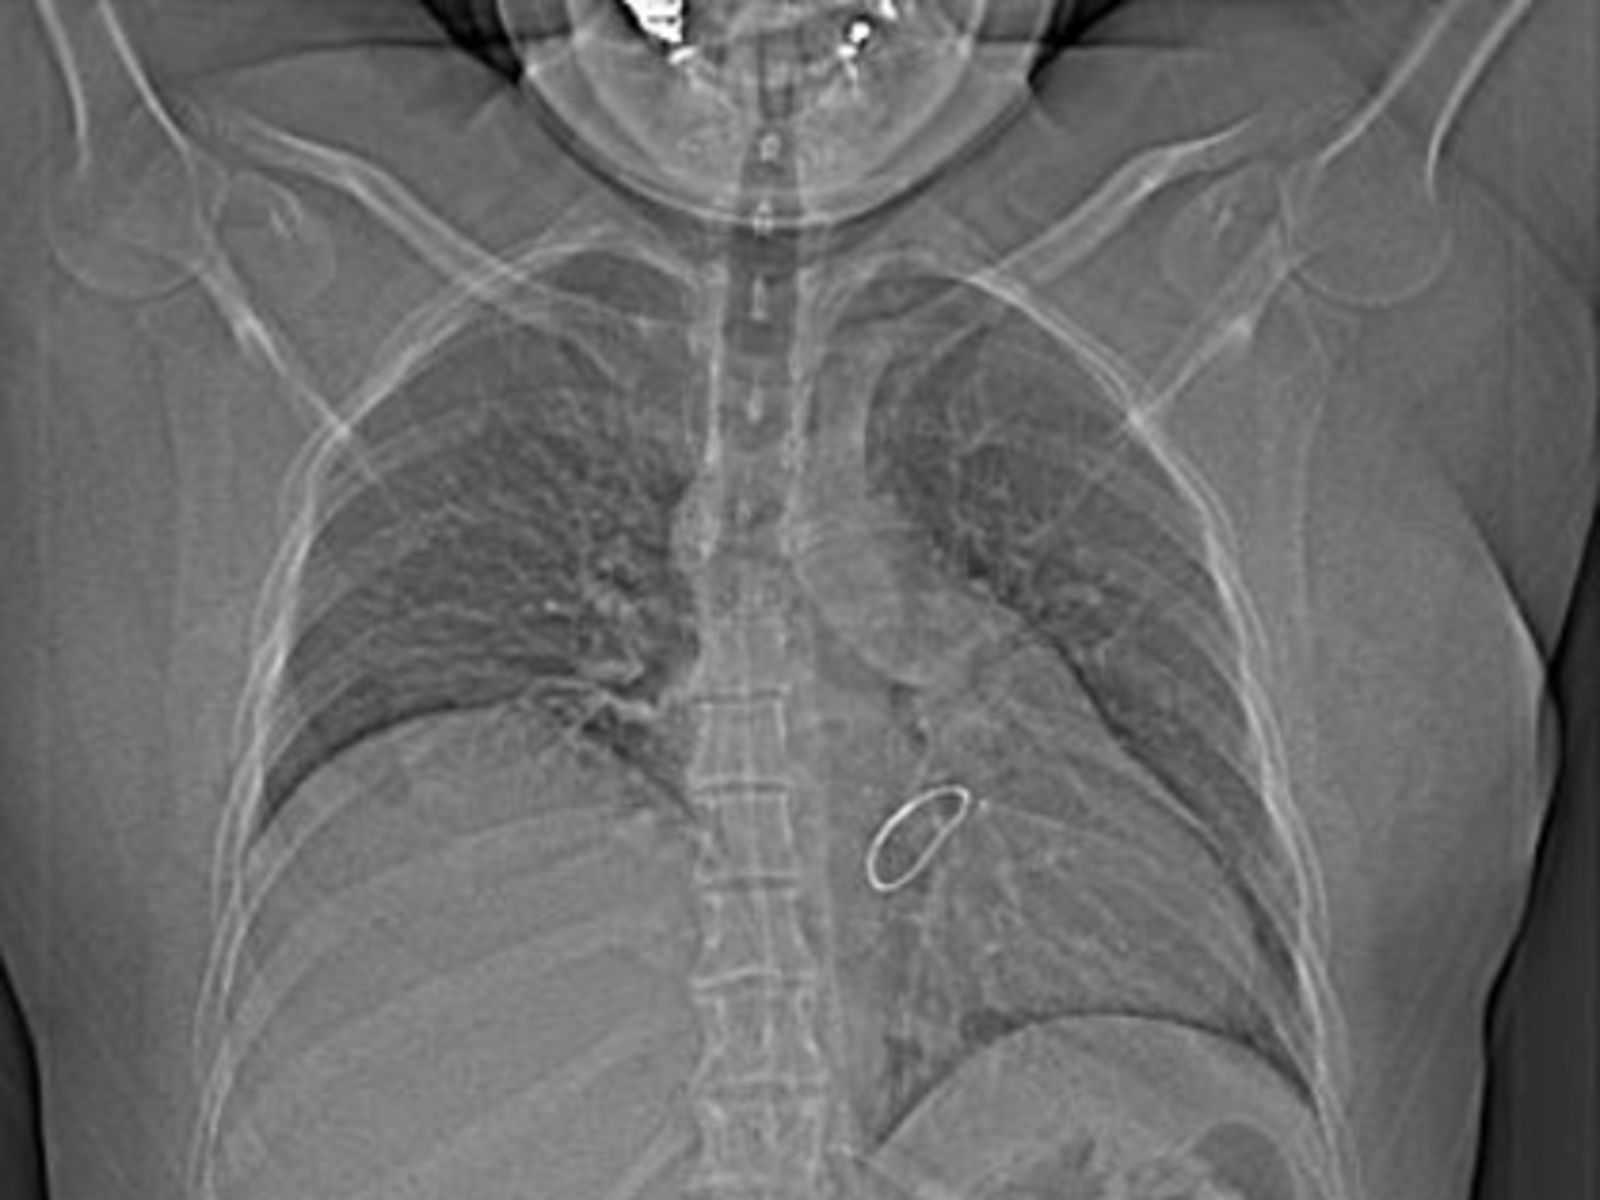

Was ist eine Zwerchfellparese?

Das Zwerchfell ist der wichtigste Atemmuskel. Wenn es teilweise oder vollständig gelähmt ist (Parese), kann es nicht mehr richtig arbeiten. Das führt in manchen Fällen zu Atemproblemen.

Welche Symptome treten auf?

Nicht jeder Patient hat Beschwerden. Etwa 50 % der Betroffenen merken nichts und brauchen daher keine Behandlung. Wenn Symptome auftreten, gehören dazu:

• Luftnot bei Belastung

• Atemprobleme im Liegen

• Luftnot im Wasser

Wie wird die Diagnose gestellt?

Um die Zwerchfellparese zu erkennen, führen Ärzte verschiedene Untersuchungen durch:

• Lungenfunktionstest

• Computertomografie (CT) des Brustkorbs

• Magnetresonanztomografie (MRT) des Halses

• Ultraschall des Zwerchfells

Welche Behandlungen gibt es?

Falls die Diagnose bestätigt wird und Beschwerden bestehen, kann eine operative Zwerchfellraffung helfen. Dabei wird das Zwerchfell gestrafft, um der Lunge wieder mehr Platz zum Ausdehnen zu geben.

Wichtig: Die Funktion des Zwerchfells kann durch die OP nicht wiederhergestellt werden, aber die Atemprobleme können deutlich verbessert werden.